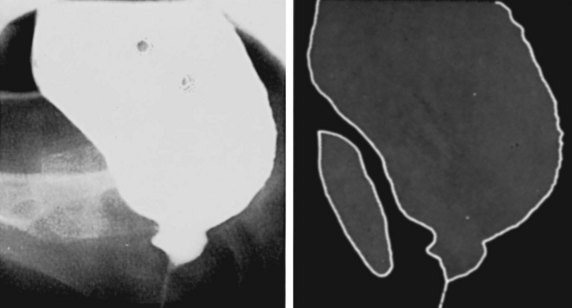

The characteristic pattern that results when a patient has a complete lesion above the sacral spinal cord is detrusor overactivity, smooth sphincter synergia (with lesions below the sympathetic outflow), and striated sphincter dyssynergia (Sullivan and Yalla, 1992; Thomas and O’Flynn, 1994; Chancellor and Blaivas, 1995b). Neurologic examination shows spasticity of skeletal muscle distal to the lesion, hyperreflexic deep tendon reflexes, and abnormal plantar responses. There is impairment of superficial and deep sensation. Figures 65-1 to 65-3 typify the cystourethrographic and urodynamic patterns. The guarding reflex is absent or weak in most patients with a complete suprasacral SCI. In incomplete lesions the reflex is often preserved but variable (Morrison et al, 2005).

After the patient recovers from spinal shock, there is generally a depression of deep tendon reflexes below the level of a complete lesion with varying degrees of flaccid paralysis. Sensation is generally absent below the lesion level. Detrusor areflexia with high or normal compliance is the common initial result, but decreased compliance may develop, a change seen in some neurologic lesions at or distal to the sacral spinal cord that most likely represents a complex response to neurologic decentralization probably involving reorganization and plasticity of neural pathways (Fam and Yalla, 1988; de Groat et al, 1997; Blaivas et al, 1998b). There is surprisingly little consensus on the evolution of the appearance or function of the bladder neck or smooth sphincter area after sacral spinal cord damage. The classic outlet findings are described as a competent but nonrelaxing smooth sphincter and a striated sphincter that retains some fixed tone but is not under voluntary control. Closure pressures are decreased in both areas (Sullivan and Yalla, 1992; Thomas and O’Flynn, 1994). However, the late appearance of the bladder neck may be “open” (Kaplan et al, 1991). Attempted voiding by straining or Credé’s maneuver results in “obstruction” at the bladder neck (if closed) or at the distal sphincter area by fixed sphincter tone (Fam and Yalla, 1988; Thomas and O’Flynn, 1994). Figure 65–4 illustrates the typical cystourographic and urodynamic pictures of the late phases of such a complete lesion.